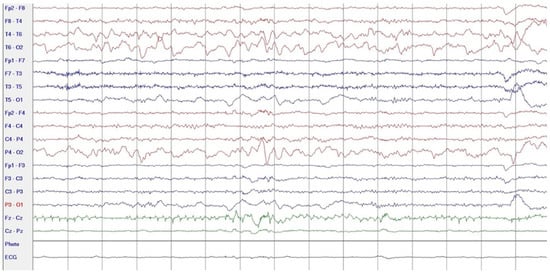

During hospitalization in the neurology ward, Holter EEG was performed in which seizure episodes corresponded to changes in the recording. Interictal EEG showed rapid activity followed by slow theta waves and several sharp and slow wave complexes (Figure 1 and Figure 2). Topiramate was added to valproic acid at a target dose of 2 mg/kg of body weight. Gradual seizure relief was observed in the following weeks, and there were no other neurological manifestations for another nine months. After that time, in December 2021, the patient was admitted to the pediatric ward due to impaired consciousness and persistent vomiting, followed by paresis of the lower limbs. A brain MRI was performed, which showed “T2/FLAIR images reveal poorly defined areas of increased signal in the brain’s white matter, both above and below the tentorium, as well as in the periventricular and subcortical regions. These areas correspond to low signal regions in T1 images. The largest change area measures 19 × 14 mm and is located in the right middle cerebellar peduncle, which merges with changes observed in the pons. Additionally, there is a lesion in the right thalamus, measuring 10 × 24 mm, along with numerous scattered foci in the corona radiata and between the basal nuclei. Overall, the imaging findings primarily suggest acute disseminated encephalomyelitis (ADEM)” (Figure 3 and Figure 4). Cerebrospinal fluid examination revealed oligoclonal bands and an elevated protein level of 118.5 mg/dL (reference range: 15.0–45.0 mg/dL) and a slightly elevated leukocyte level of 29/mm3 (lymphocytes 72.4%, neutrophils 27.6%).

Figure 1.

EEG trace: rapid intraictal rate (December 2020).

Figure 2.

EEG recording: postictal theta waves (December 2020).